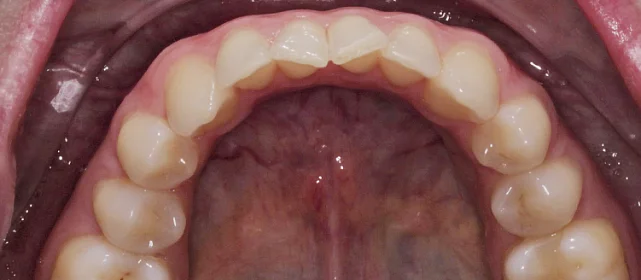

Зубы выровнены, смыкание нормализовано. Установлены несъёмные ретейнеры на обе челюсти, изготовлены ретенционные капы. Пациентка предварительно проконсультирована ортопедом онлайн.

Решение: Поставили элайнеры 3D Smile на обе челюсти. Лечение заняло 4 года и потребовало нескольких последовательных этапов коррекции. Капы менялись каждые 1–2 недели, на контрольных визитах отслеживали прогресс и выдавали новые наборы. Зубы встали в правильное положение, смыкание нормализовалось. Зафиксировали ретейнеры на обе челюсти, изготовили ретенционные капы. Пациентка прошла онлайн-консультацию с ортопедом для оценки дальнейших шагов.

Лечение потребовало нескольких последовательных этапов — каждый дозаказ кап уточнял положение зубов, которые не полностью отреагировали на предыдущий курс. Элайнеры 3D Smile позволяют работать поэтапно, корректируя план по ходу. Результат получен, ретейнеры зафиксированы. Рекомендовала пациентке консультацию ортопеда для оценки состояния зубов после лечения